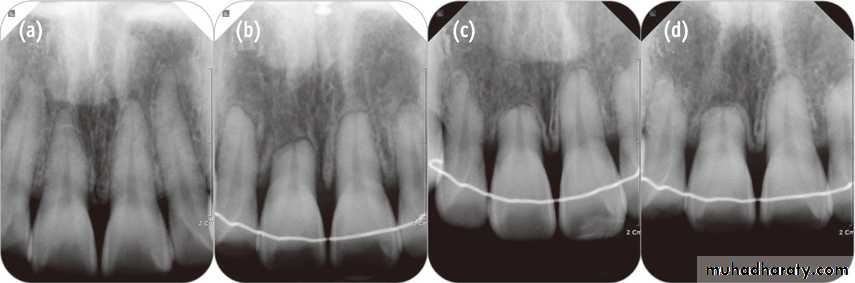

Periodontal gingivitis, periodontitis, gingival recession or hypertrophy, alveolar bone loss,dehiscences, fenestrations,

Dental crown: decalcifications, decays, tooth wear, enamel cracks and fractures;discolorations, deterioration of prosthetic crown (as fracturing a ceramic one duringdebonding). root: root resorption, early closure of root apex, ankylosis. pulp: ischemia, pulpitis, necrosis.